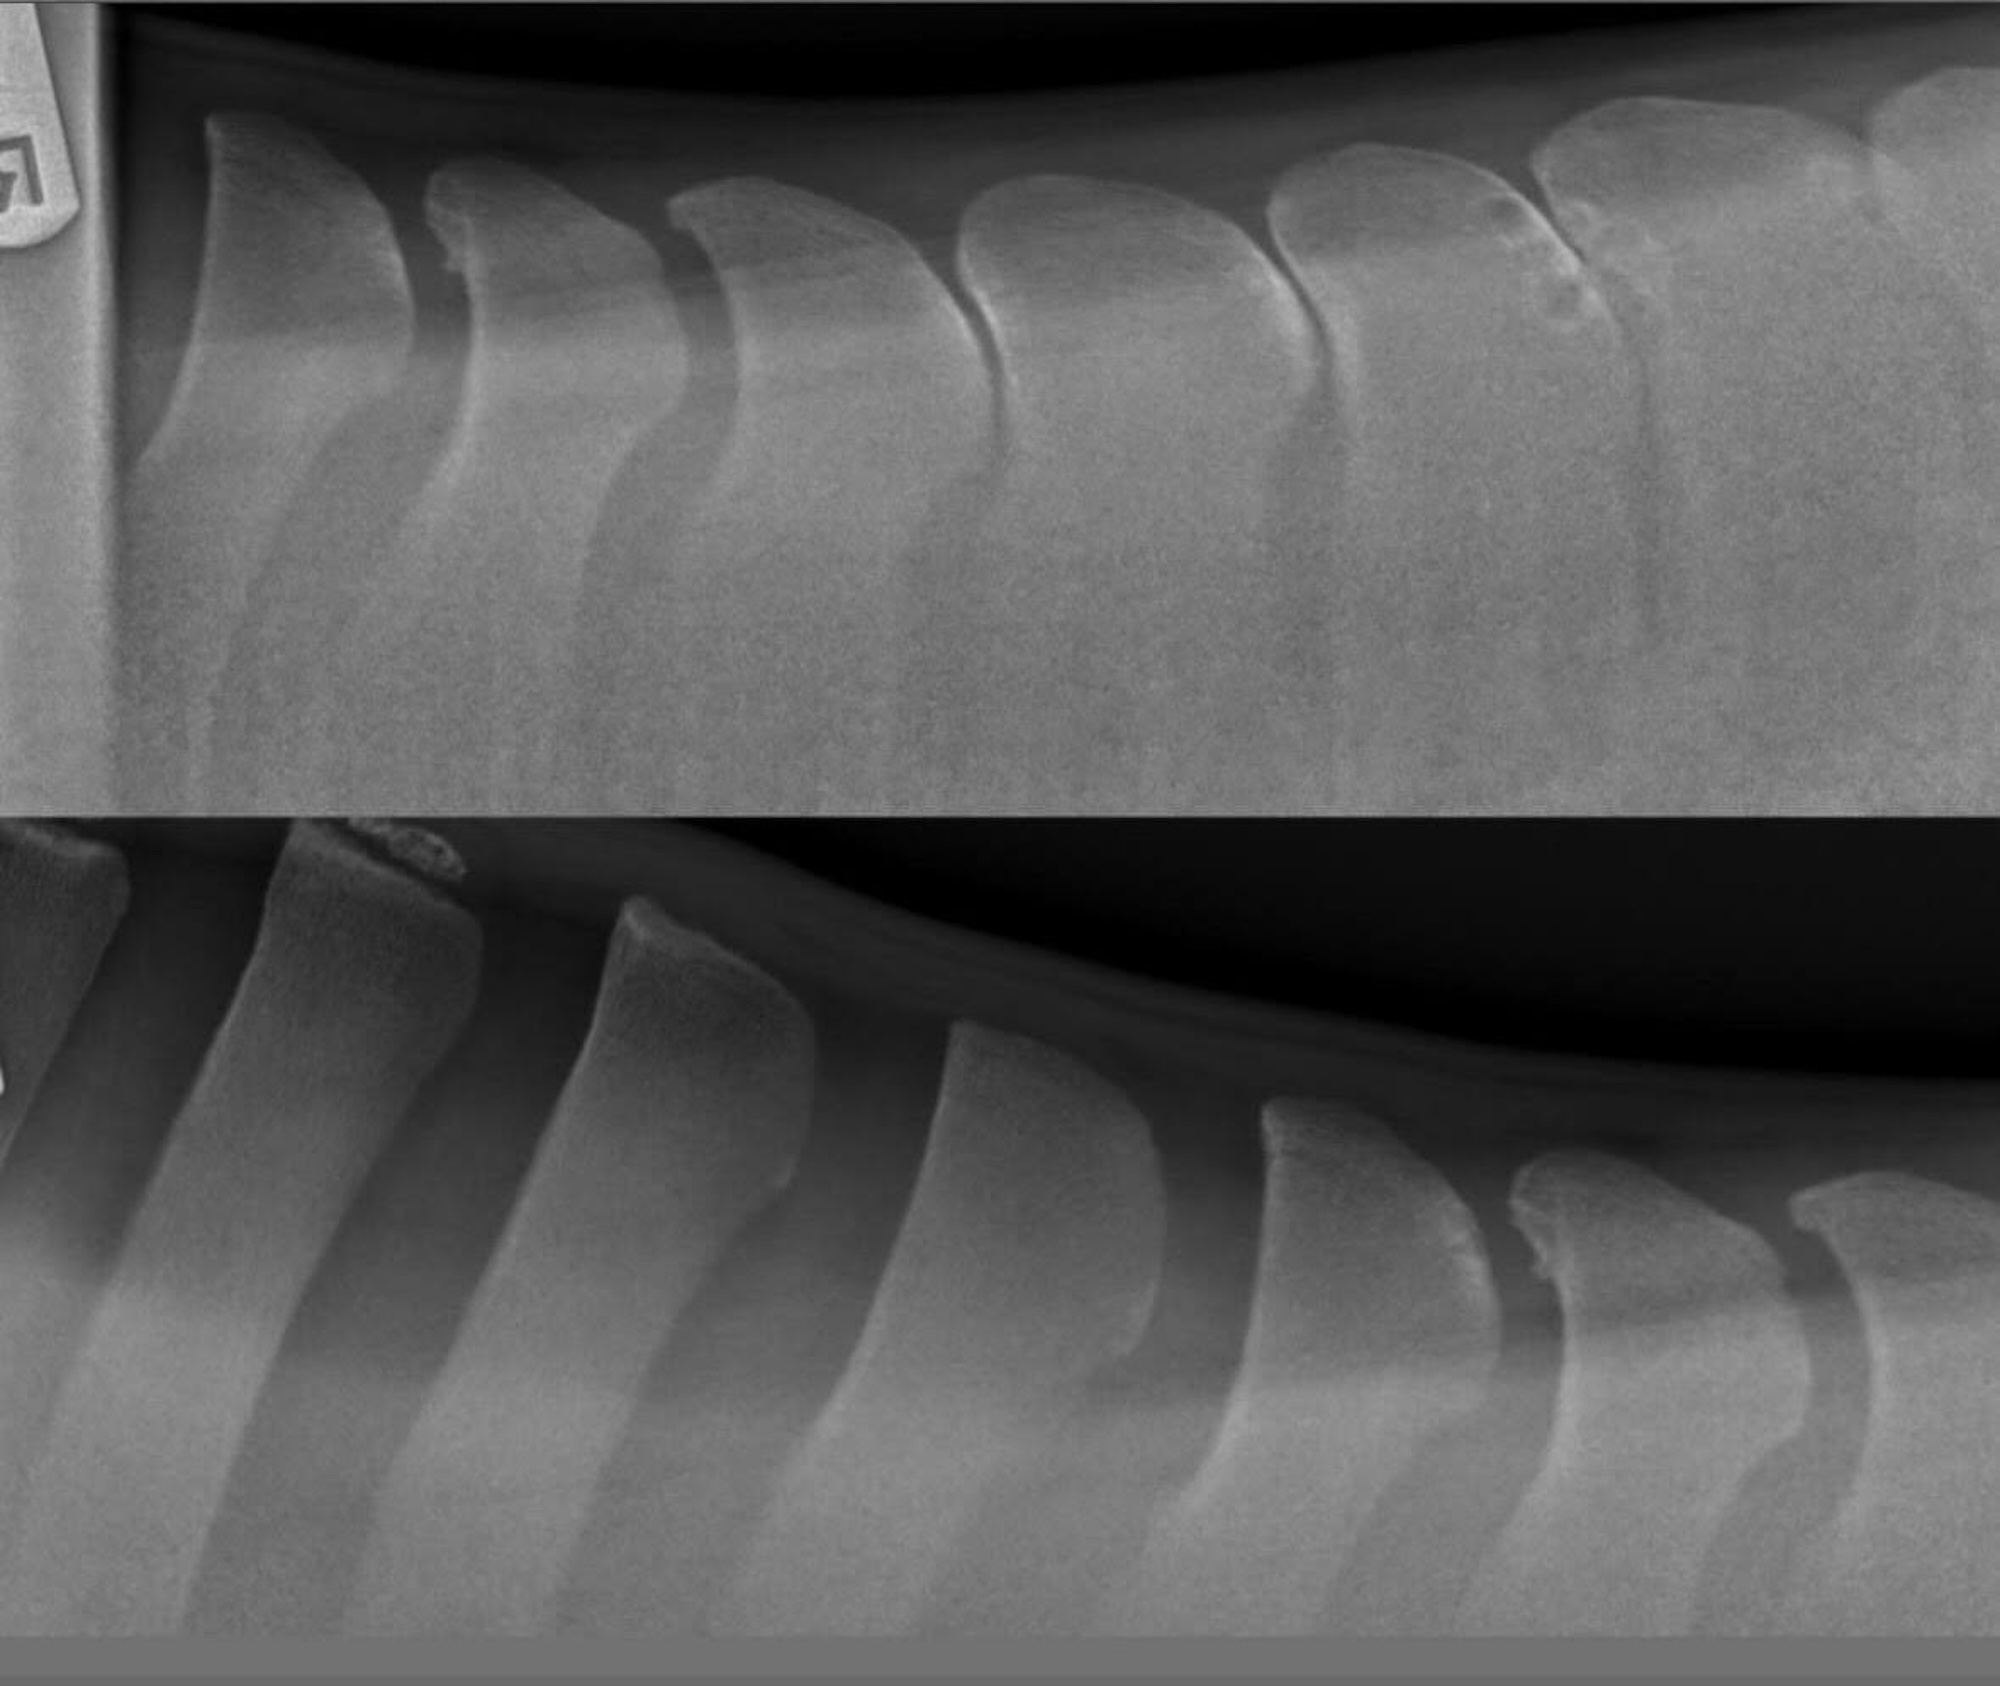

Louie’s kissing spines were operated on

“Even when the vet was watching him trot, he didn’t think it was kissing spines – until we had the X-rays,” April said. “They put him about eight out of 10 for pain and it was massive, through the whole of his spine.

“I opted for the surgery – he needed bone shaving and ligament snips – because the vet said he was only young, and it was so severe, medication wasn’t going to make a difference.”